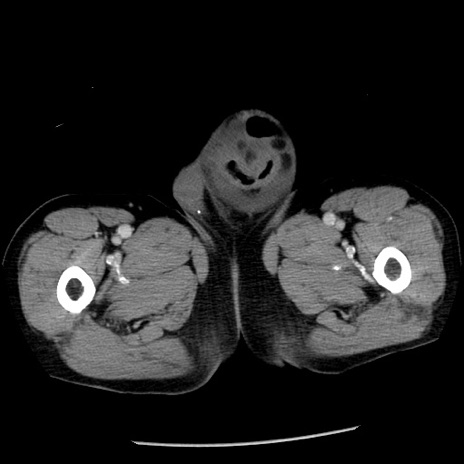

症例26(横断像)

【症例】80歳代男性

【主訴】嘔吐

【現病歴】昨晩2回嘔吐あり、今朝になっても嘔吐あり。来院。

【既往歴】胃潰瘍

【身体所見】意識清明、BT 37.6℃、BP 166/95mmHg、HR 100bpm、SpO2 97%、腹部:平坦・軟、腸蠕動音聴取良好、圧痛なし。

【データ】WBC 21900、CRP 1.46